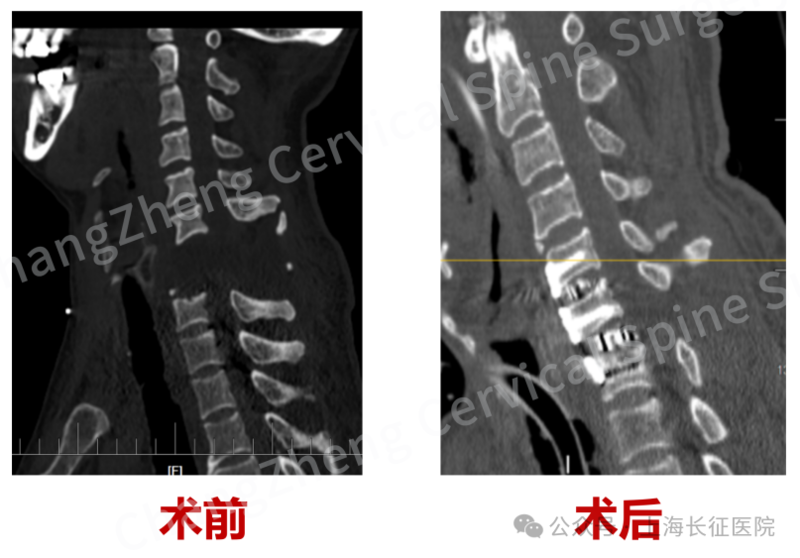

影像检查显示患者颈椎罕见大跨度脱落

术前、术后影像对比,手术效果良好